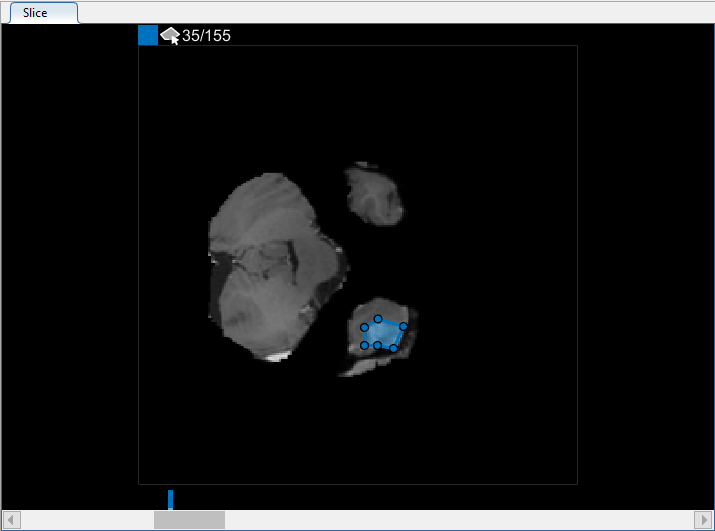

Можно также просмотреть каждый срез объема в панели Среза. Используйте ползунок в нижней части панели, чтобы переместиться от среза до среза. Вы видите опухоль на срезе 35 через срез 88. По умолчанию панель Среза отображает объем, ориентированный вдоль оси X-Y, но можно изменить это использование кнопки в разделе Orientation панели инструментов на вкладке Segmenter. Панель Среза также, где вы используете инструменты для рисования, чтобы задать маску.

В панели Среза перейдите к срезу, где объект сначала появляется, срез 35, и чертите схему вокруг объекта. В данном примере используйте инструмент для рисования Многоугольника. Щелкните, чтобы создать вершину, затем переместите курсор и щелкните еще раз, чтобы создать вторую вершину прямой линией, соединяющей их. Продолжите этот процесс, чтобы создать связанную линию. Чтобы добавить дополнительные вершины после того, как вы закончите чертить, дважды кликните на ребре ROI.